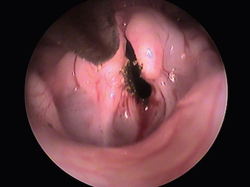

Perilaryngeal tumors are not discovered until the cat develops respiratory stridor (Figure 5A). At this stage, open-mouth breathing may be present and the cat in a respiratory crisis. A video-otoscope can be a very useful tool in viewing this area and assessing the airway stricture. Biopsy forceps can pass through the working channel for tissue sampling.

The CO2 laser, with a special tip that goes through the video-otoscope, can be used to treat these lesions and relieve the immediate respiratory crisis (Figure 5B). The ultimate treatment will depend on the histopathologic diagnosis.

Perilaryngeal tumors

Figure 5A

Reoving lesions witha CO2 laser and video otoscope

Figure 5B